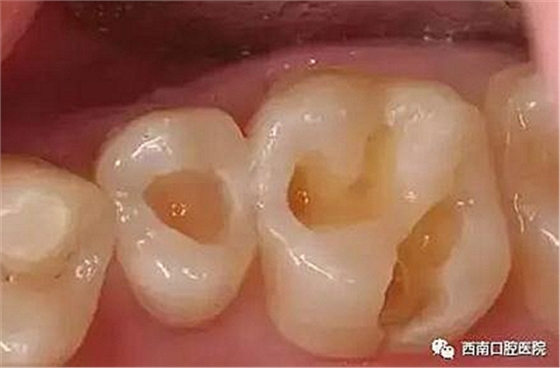

我們來看下各個材料充填之后的顏值吧!

樹脂、石英或其他硬度較高的礦物混合形成的復合樹脂材料顏色更接近天然牙,有不同色調可選擇,用于前牙修復時有明顯優(yōu)勢,可以替代銀汞合金。